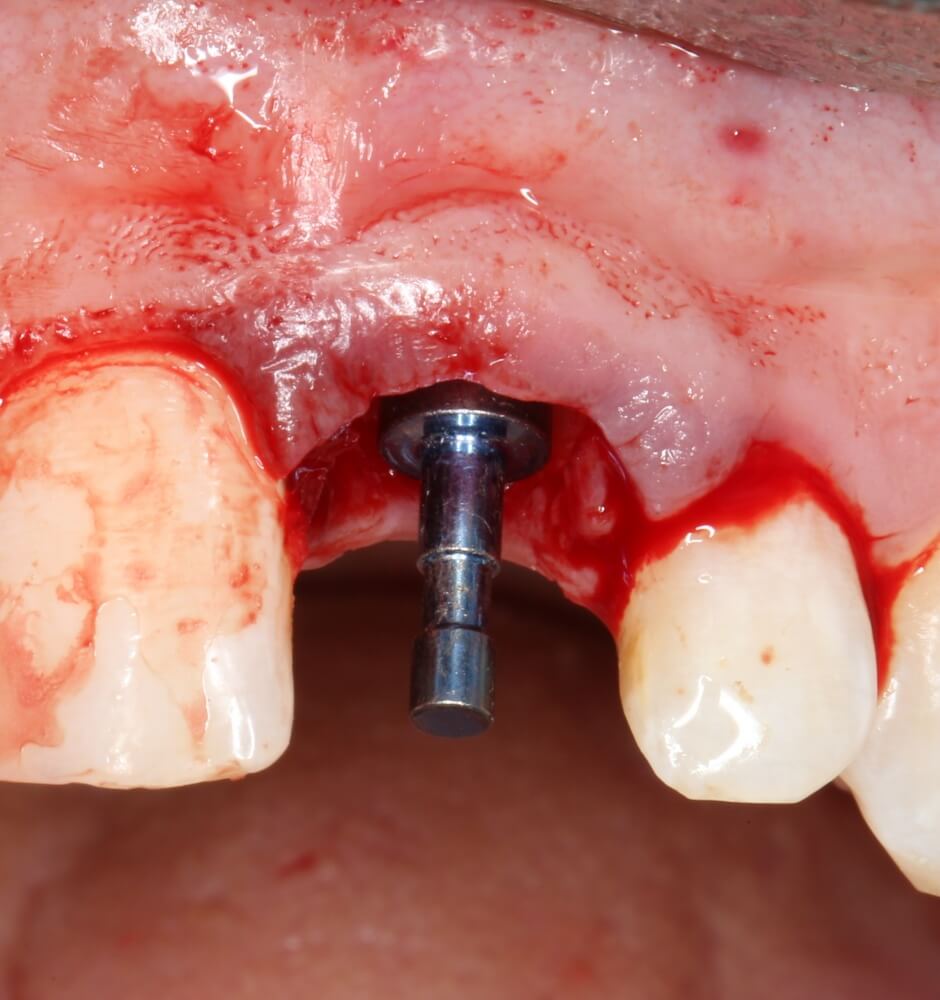

Установка имплантатов

По ряду уже упомянутых выше причин, для решения этой клинической задачи мы выбрали имплантаты Xive. Лунки для них мы уже приготовили. возможную первичную стабильность оценили. Имплантаты мы установили с усилием чуть больше 15-20 Нсм — такого крутящего момента более, чем достаточно, особенно если учесть, что временные коронки будут соединяться между собой.

Подробно о том, что такое крутящий момент и хирургический протокол можно прочитать здесь>> и тут>>, соответственно. Из-за использования специальных индивидуализируемых временных абатментов, имеющих только три положения, нам нужно позиционировать платформу имплантатов по граням. Это очень просто  — мы выводим вырез абатмента TempBase (он входит в комплект поставки) вестибулярно.

После перкуторной проверки стабильности имплантатов и точности позиционирования, мы переходим к следующему этапу — сохранению десневого контура.

Установка имплантатов занимает около двух минут.